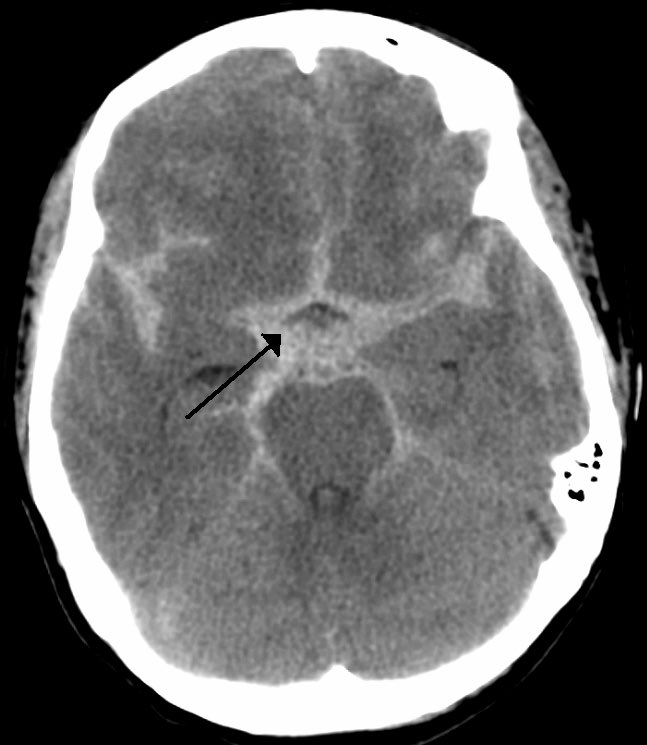

▫️Subarachinoid hemorrhage🩸🧠

✳️Blood in cisterns and fissures that resemble spider 🕷 shape